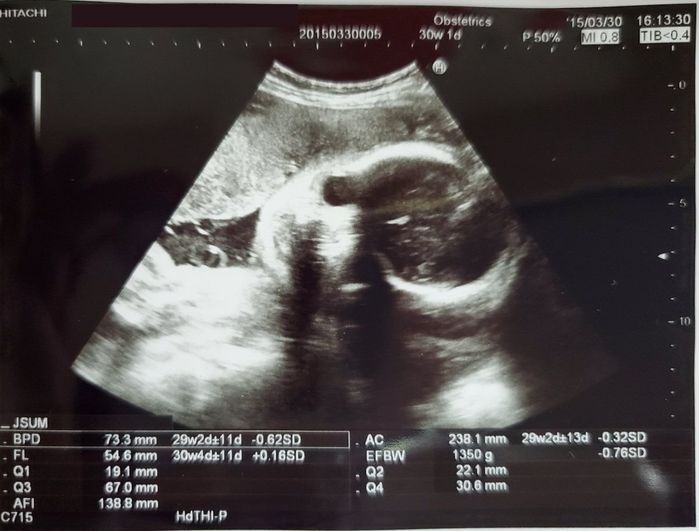

妊娠30週目のエコー写真 - ぐんぐん成長中!

今回のエコーでもこちらを向いています。この写真は特に見つめられているように感じました。夫と毎回「見られているね!」と話していました。

このころは健診ごとにググっと成長し、体が画面から大きくはみ出してしまいました。実はこの前日の夕方に強い腹痛が起こり病院に向かい、そのまま切迫早産で緊急入院。4日後に退院できましたが、1カ月ほど自宅安静となってしまったのです。